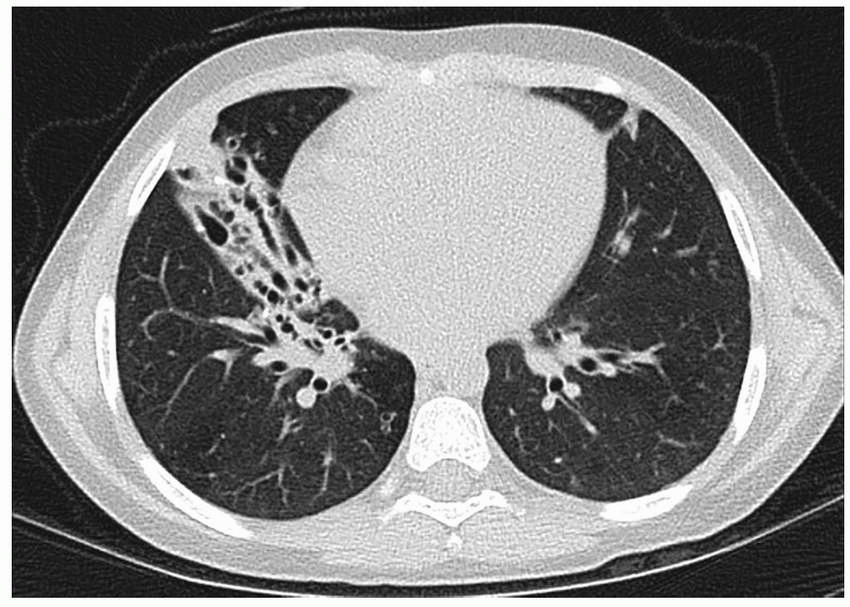

From www.researchgate.net

(PDF) Recurrent chest infections in two young nonsmoker men Recurrent Chest Infection In 2 Year Old It's usually mild and can be treated at home, but it can be. What are the signs and symptoms of a chest infection (pneumonia?) the signs and symptoms depend on what caused the infection and the. You should take them to a gp, or you. Read about chest infections, including the symptoms, what you can do to treat it yourself,. Recurrent Chest Infection In 2 Year Old.

From radiologykey.com

Pediatric Lower Respiratory Tract Infections Radiology Key Recurrent Chest Infection In 2 Year Old Read about chest infections, including the symptoms, what you can do to treat it yourself, and how a pharmacist and gp can help. Bronchiolitis is a common chest infection that affects babies and children under 2. If your child's temperature is very high, or they feel hot and shivery, they may have a chest infection. You should take them to. Recurrent Chest Infection In 2 Year Old.